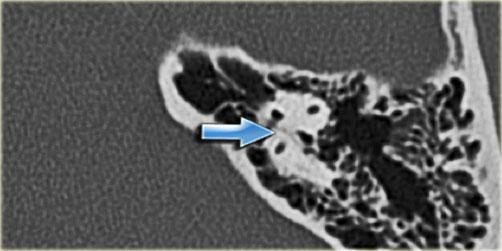

Bên trái là hình ảnh của một bệnh nhân nam 58 tuổi.

Mũi tên màu xanh chỉ cống ốc tai đi về phía ốc tai.

Hình ảnh này có thể bị nhầm lẫn với đường gãy xương (mũi tên).

Lưu ý có hình ảnh mờ đục của hòm nhĩ và các tế bào khí xương chũm.